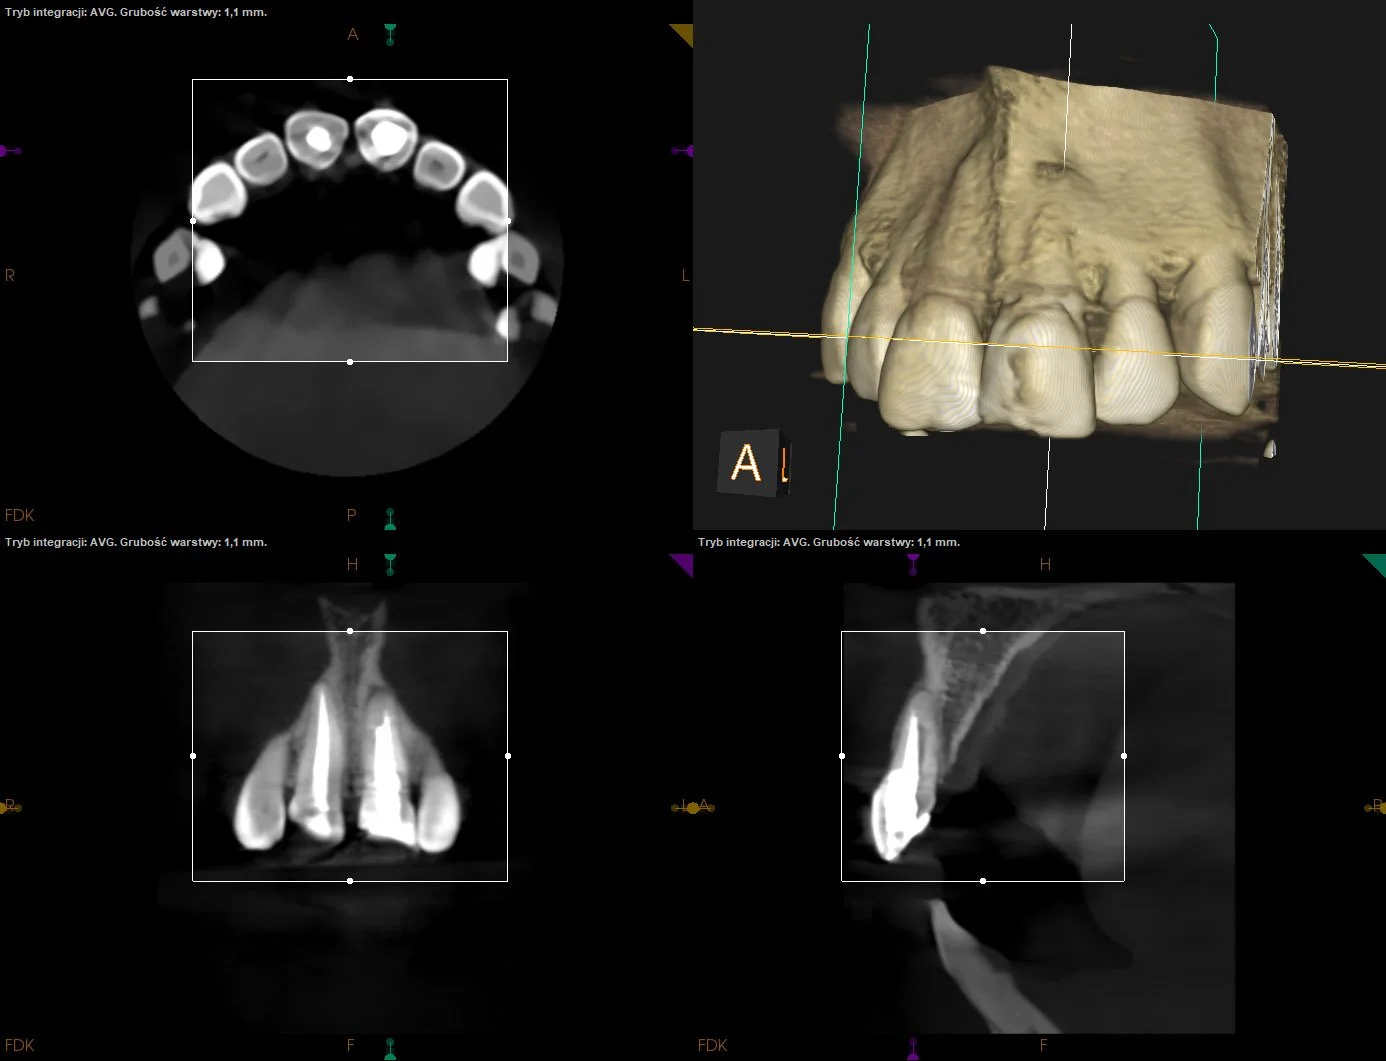

Warunkowe reendo d.21 - stan po urazie w dzieciństwie z intruzją i następową repozycją siekaczy centralnych.